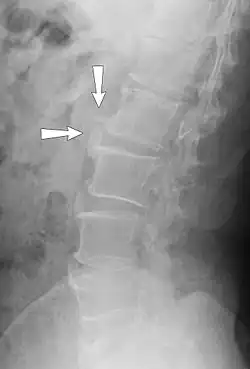

X-ray of spondylosis of the lumbar spine

Workplace exposures to whole-body vibrations for long durations can lead to musculoskeletal problems of many kinds.[9] Problems of the neck and lower back in particular can be common for operators of heavy equipment including construction, forestry, agriculture, and trucking. Other occupations where whole-body vibrations may be present include aircraft operators, sea vessel workers, drivers of public transportation like trains and buses.

Farmers with long-term exposure to whole body vibration and mechanical shocks have a higher prevalence of back pain (compared to those not exposed to vibration), and the prevalence increases with vibration dose.[10] Long-term exposure affecting the whole body leads to spinal degeneration (spondylosis) and increased risk of low back pain.[11][12]